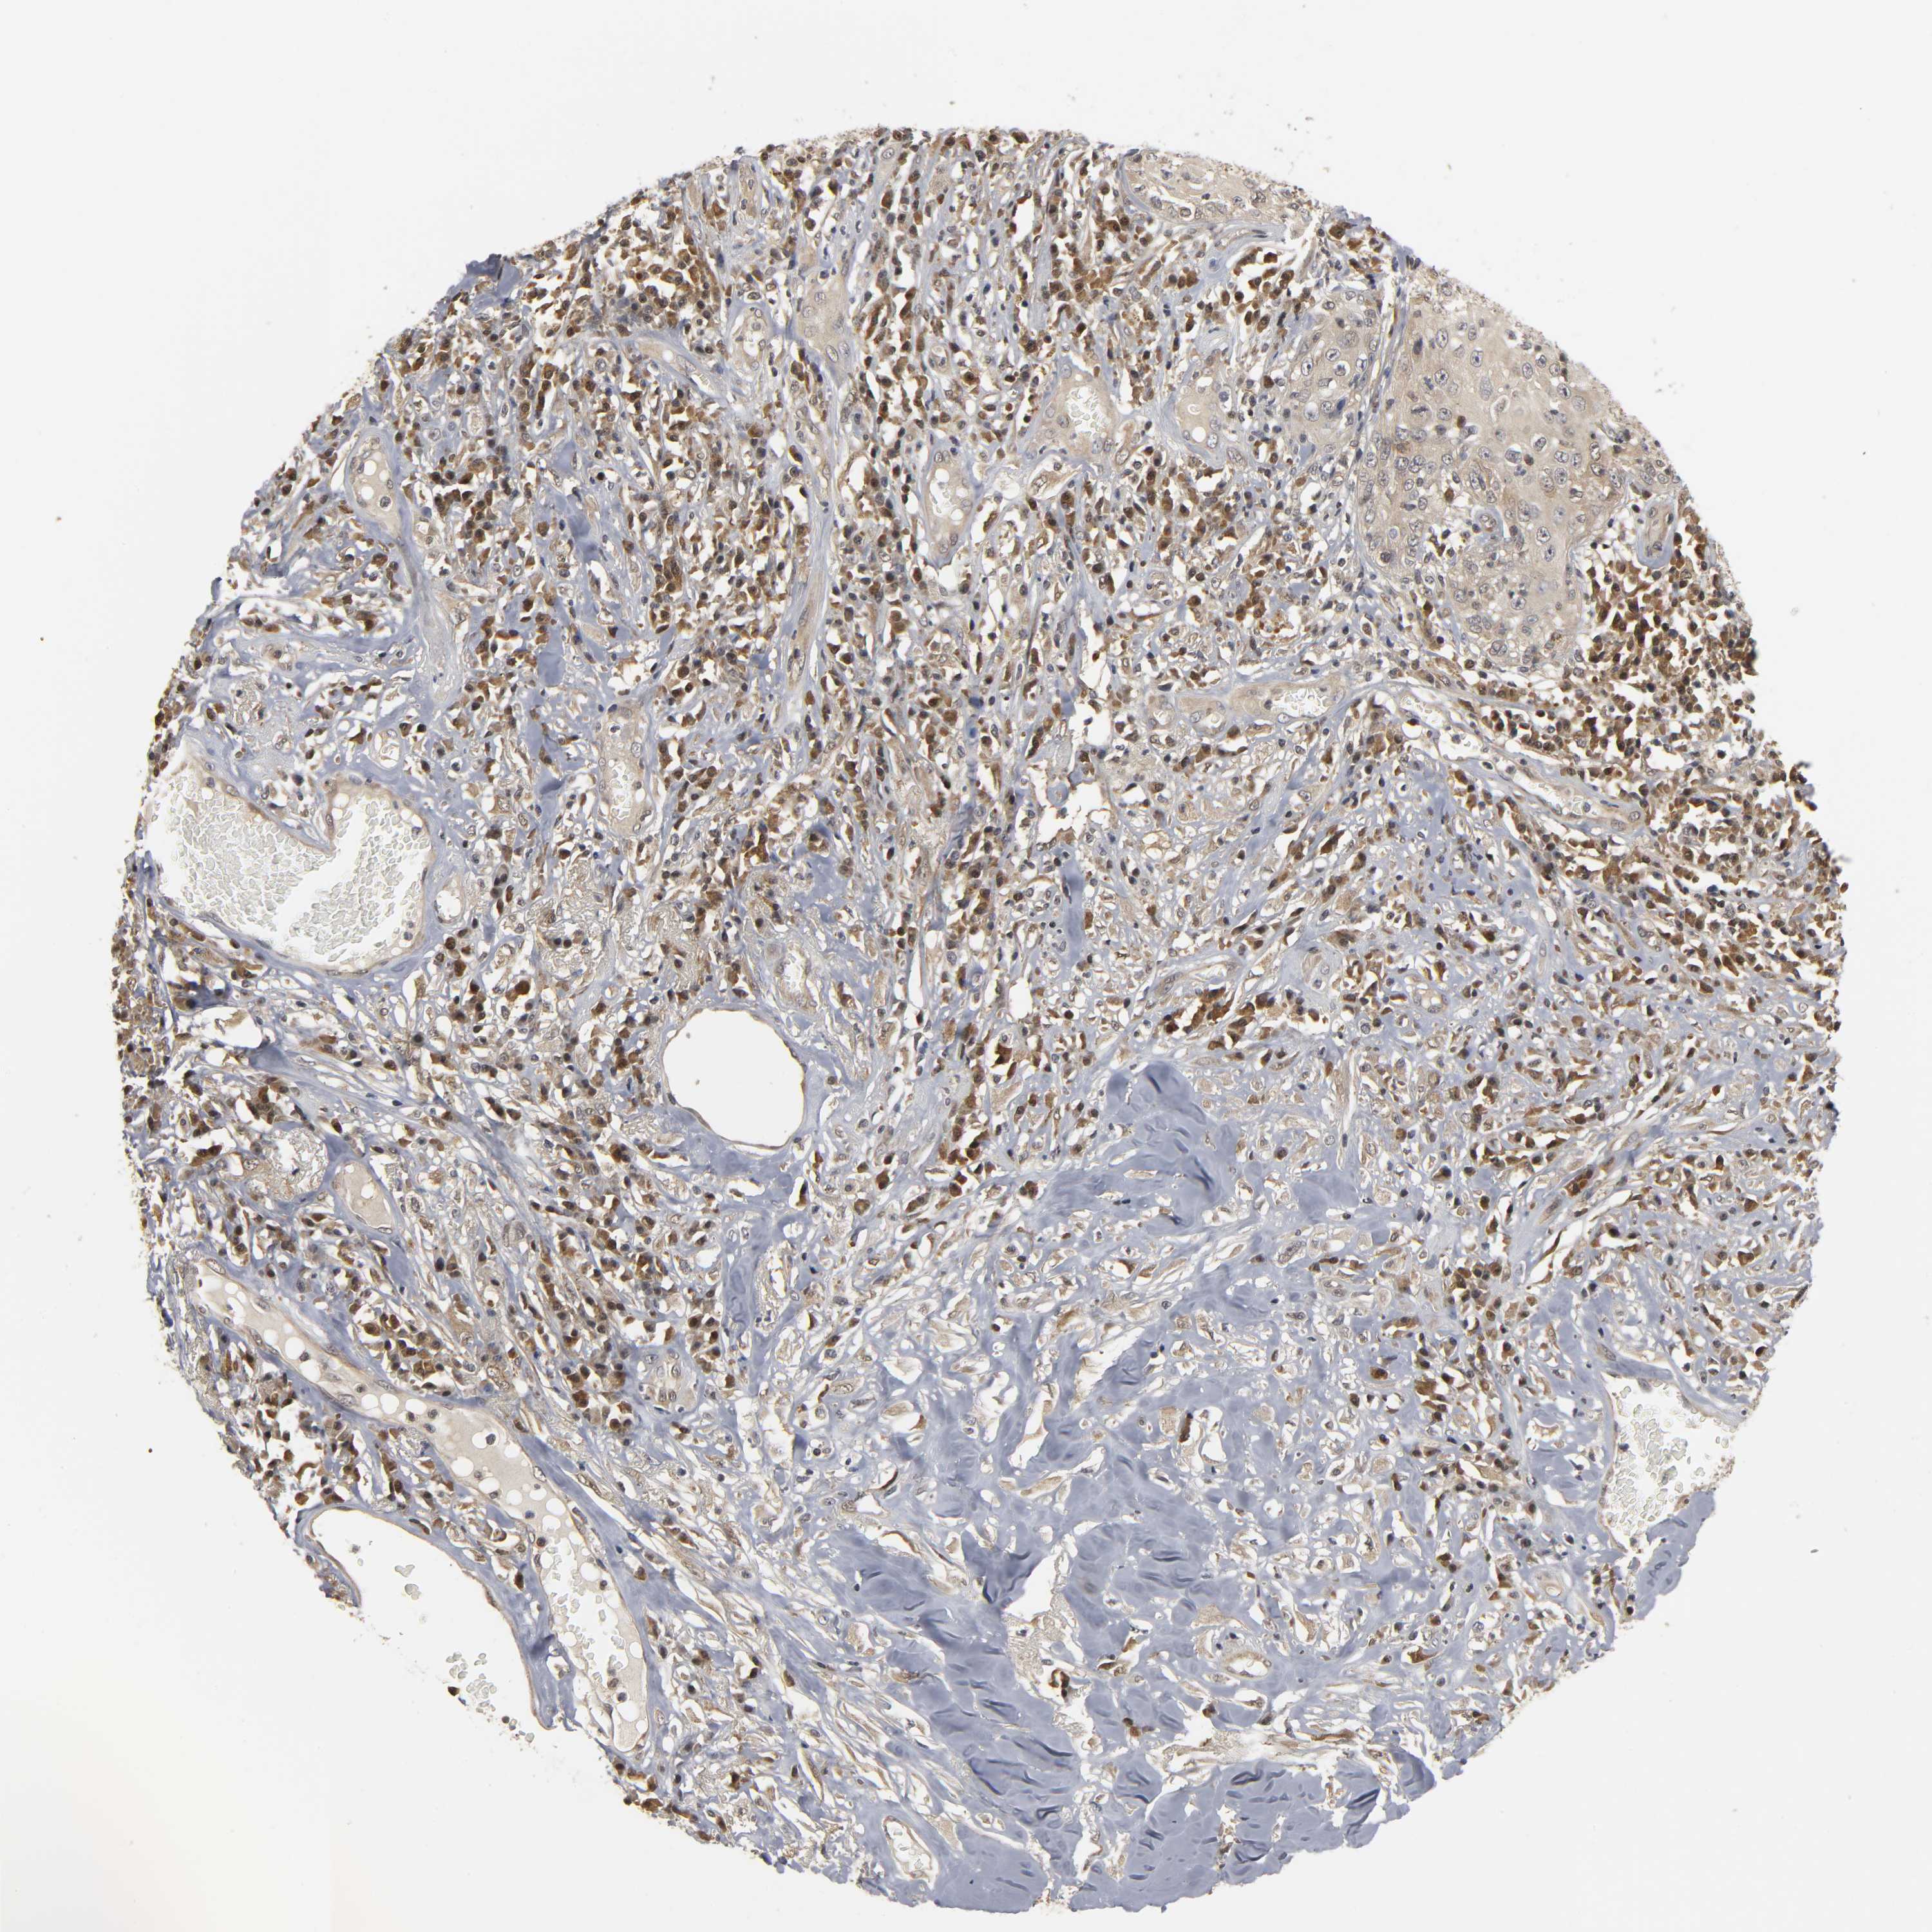

SKIN CANCER - Protein expressioni

A mouse-over function shows sample information and annotation data. Click on an image to view it in a full screen mode. Samples can be filtered based on level of antibody staining by selecting one or several of the following categories: high, medium, low and not detected. The assay and annotation is described here.

Antibody stainingi

Antibody staining in the annotated cell types in the current human tissue is reported as not detected, low, medium, or high, based on conventional immunohistochemistry profiling in selected tissues. This score is based on the combination of the staining intensity and fraction of stained cells.

Each image is clickable and will lead to virtual microscopy that enables deeper exploration of all samples and also displays staining intensity scores, fraction scores and subcellular localization as well as patient and tissue information for each sample.

Antibody HPA004190

Antibody CAB005870

Squamous cell carcinoma, NOS

Basal cell carcinoma